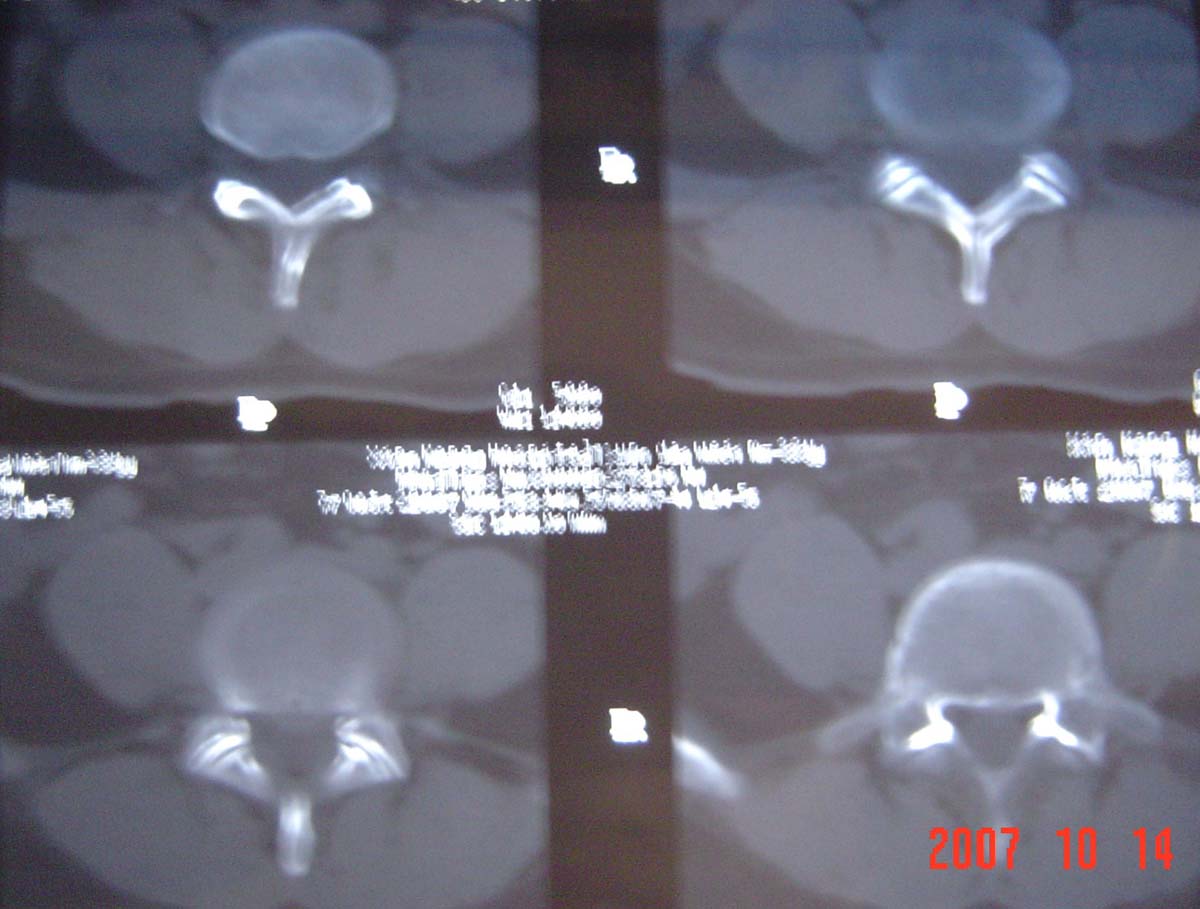

本人的片子,腰腿痛多年,时轻时重。请各位老师发表高见!

1.l4~5间盘膨出伴突出(中央型)

2.l5-s1后纵韧带钙化.